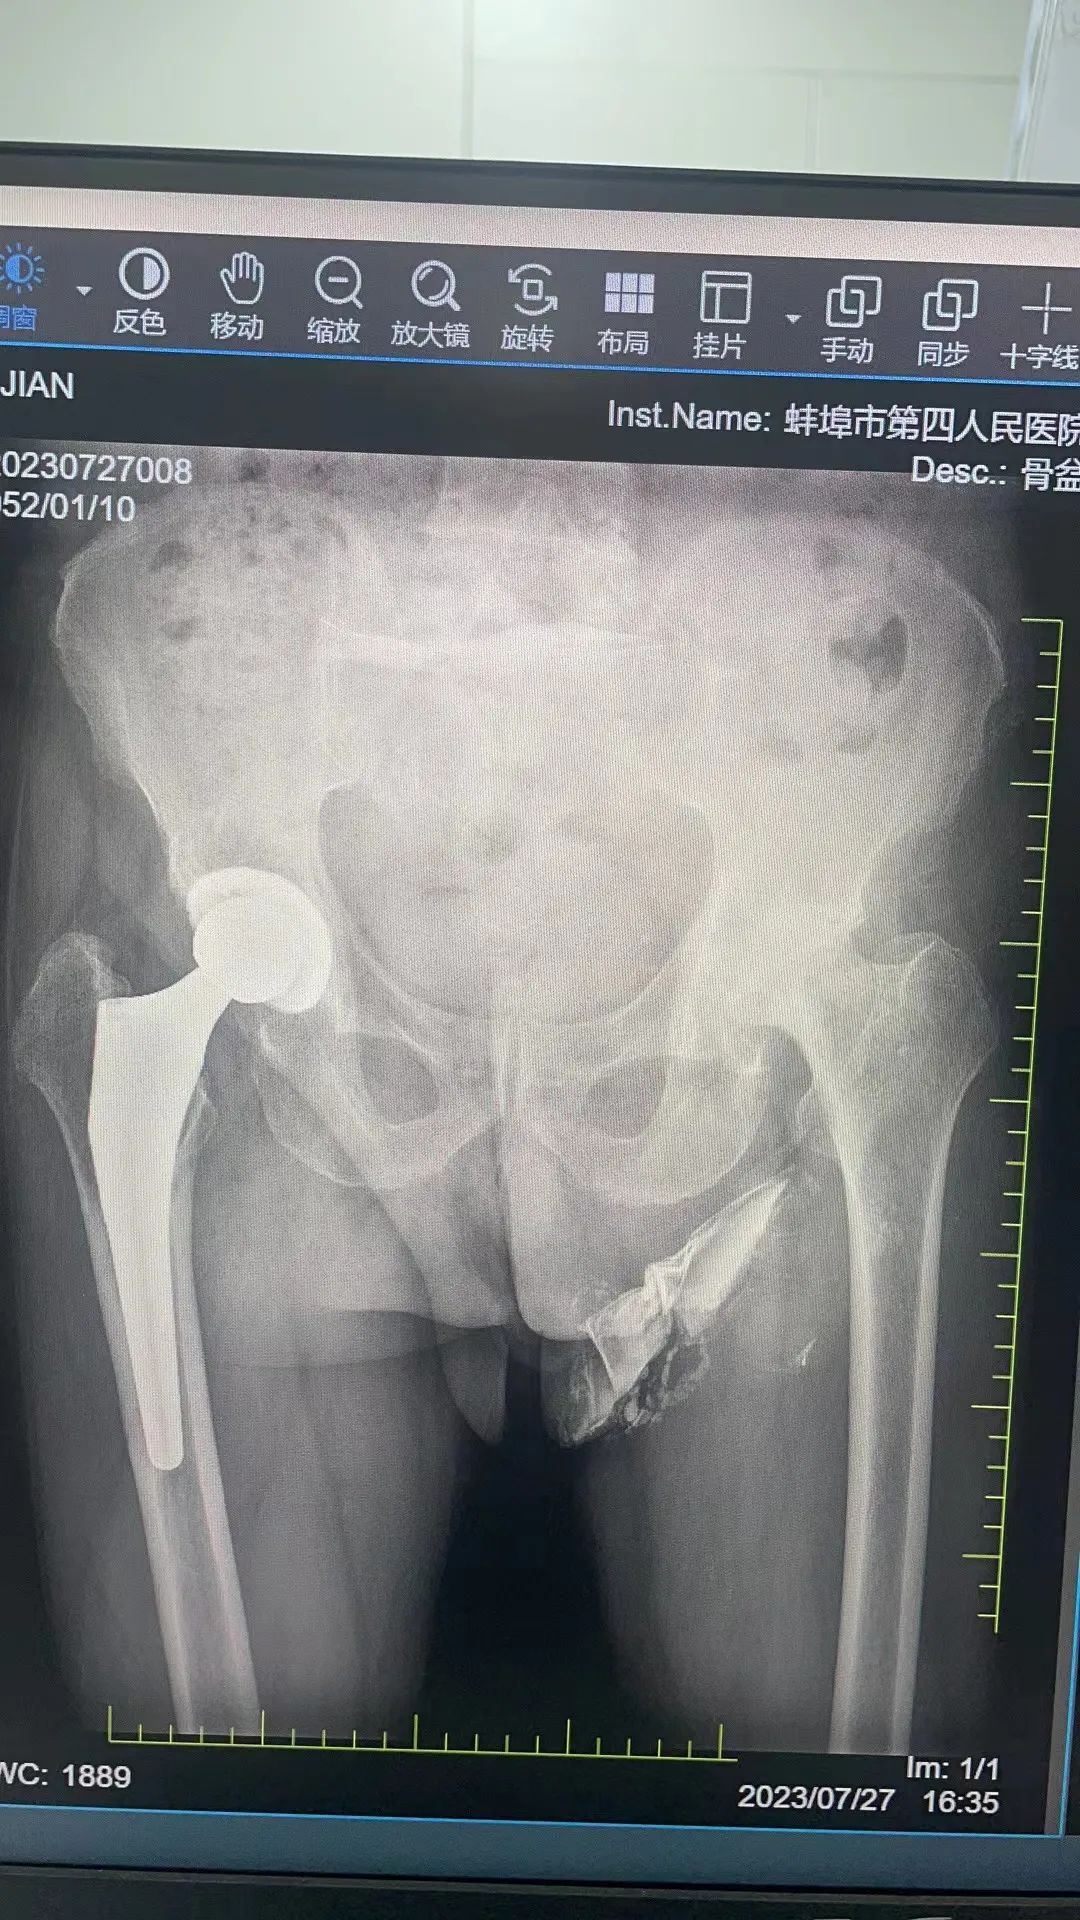

患者耿某,男,71岁,左侧股骨头无菌性坏死,冠心病,高血压,心力衰竭,既往身体较差。7月28日收住入院,入院后经内科、康复、急诊ICU,麻醉科等多学科会诊,给予有效的评估及宝贵的处理意见,并经过一周的调整及准备后,于8月7日在椎管内麻醉下行左侧全髋关节置换术。术后3天患者自行用助步器辅助下床行走,现已康复出院。